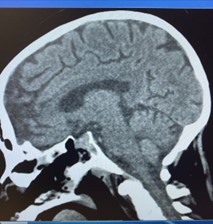

Case Illustration